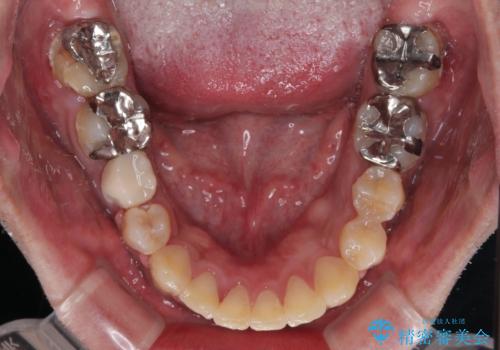

元々むし歯リスクが高かった上に、矯正治療中も磨き残しが多かったため、今後はむし歯治療を行う必要があります。

- 治療中は歯磨きがしにくくなるため、虫歯や歯周病になりやすくなります